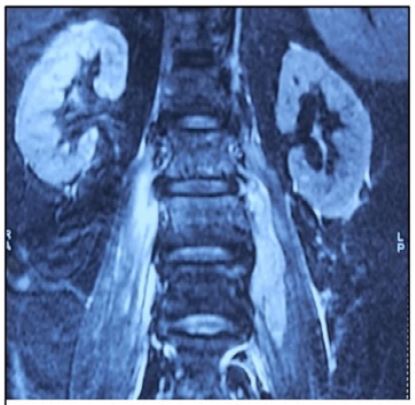

Figure 1: MRI spine with L2-L3 spondylodiscitis with bilateral psoas abscess.